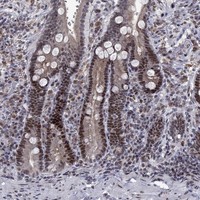

Immunohistochemical staining of human duodenum shows moderate nuclear positivity in glandular cells.